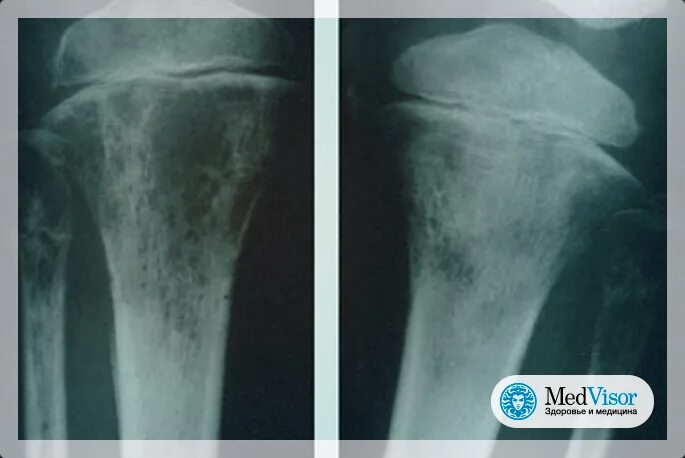

Химиотерапия при метастазах в костях